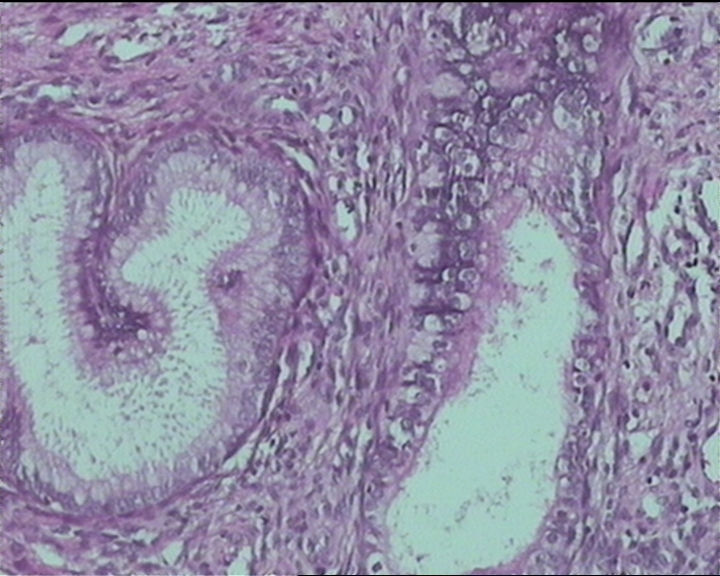

54岁女性,临床“宫颈息肉”送检;巨检:组织一块1。5*1CM,灰红。